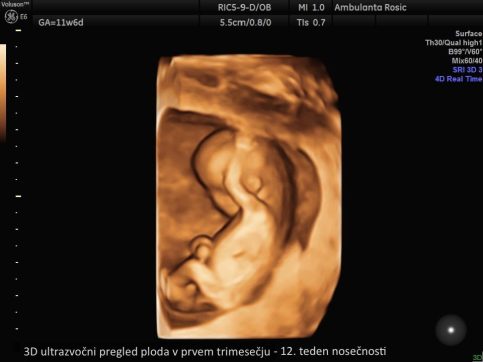

V prvem trimesečju lahko 3D/4D ultrazvočni pregled ploda opravimo ob prvem pregledu ali hkrati z meritvijo nuhalne svetline. Pri 3D/4D ultrazvoku v drugem in tretjem trimesečju nosečnosti določimo tudi lego ploda, položaj posteljice, količino plodovnice, preverimo rast in telesno težo ploda, izmerimo pa lahko tudi pretoke skozi popkovnične žile z Dopplersko ultrazvočno preiskavo za oceno stanja ploda. 3D/4D ultrazvok ploda lahko opravimo tudi ob morfologiji ploda.

3D/4D ultrazvok v nosečnosti izvajamo z vaginalnim (nožničnim) ali abdominalnim (trebušnim) tipalom. Vaginalno tipalo uporabljamo pri ultrazvočni preiskavi v prvem trimesečju, abdominalno tipalo pa v drugem in tretjem trimesečju nosečnosti. S tem imate pri nas nosečnice možnost opraviti 3D/4D ultrazvok ploda že od prvega pregleda v nosečnosti dalje.